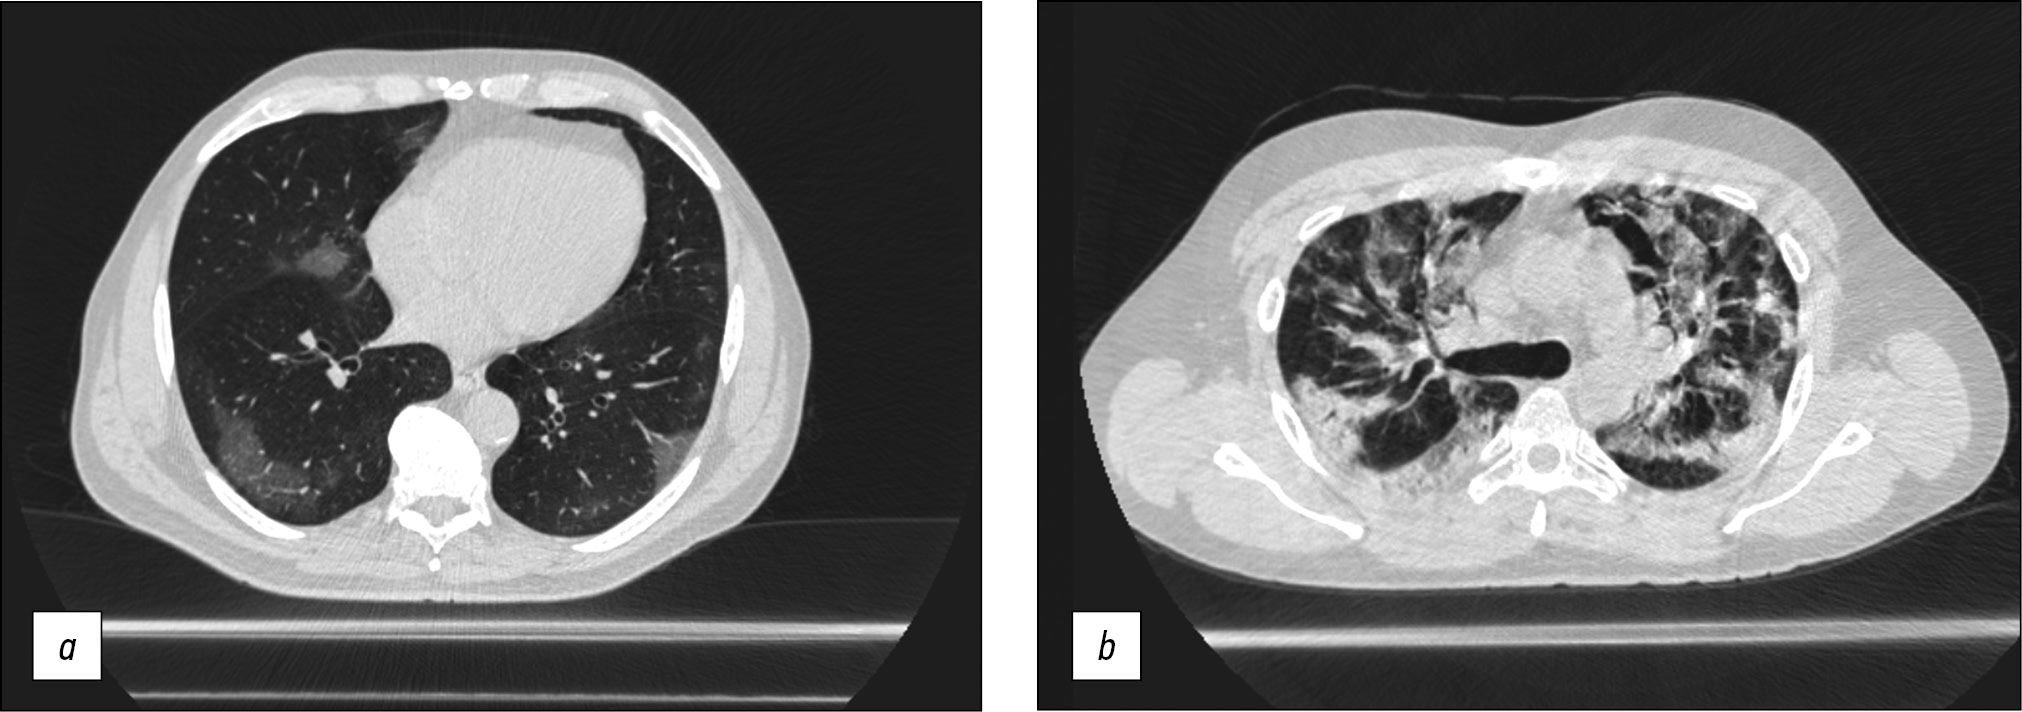

Chest CT was conducted in the majority of cases to obtain a diagnosis or to provide continuing observation for patients with COVID-19 pneumonia. The scanning parameters (Table 1) enable us to obtain images of adequate quality to differentiate between viral pneumonia, cardiogenic pulmonary edema, and bacterial pneumonia. Fig. 5 shows CT data for COVID-19-associated viral pneumonia patients.

Fig. 5. Axial computed tomographic slices of chest organs in the lung window: (a) polymorphic, predominantly subpleural areas of ground-glass opacity, corresponding to the CT image of viral pneumonia (including COVID-19), CT-1, and (b) multiple polymorphic areas of parenchyma compaction with a tendency to merge, with ground-glass opacity areas and mild reticular changes, CT-3.

A mobile CT generated acceptable quality chest CT images detecting viral pneumonia (see Fig. 5 a), and the patient capacity was sufficient for a temporary hospital with 1,300 beds in overload circumstances. The peak load was 110 scans per day, with an average of 44. This system differs from modular and mobile CTs mounted on trailers [7], mostly due to the use different types of CT.